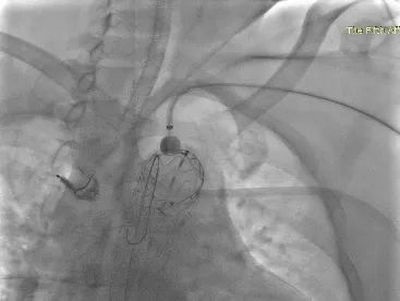

▲ 术后造影

手术方式确定后,快速完成术前准备,在全麻下行在其胸主动脉植入覆膜支架,同时在左锁骨下动脉原位开窗,植入分支支架。体内开窗完成仅用几秒钟,整个手术过程耗时2小时,患者只是在右股部开2mm的穿刺口和左上肢3cm的切口。术后,患者意识清醒安全返回病房,2天后即可下床活动,手术取得了良好的治疗效果。